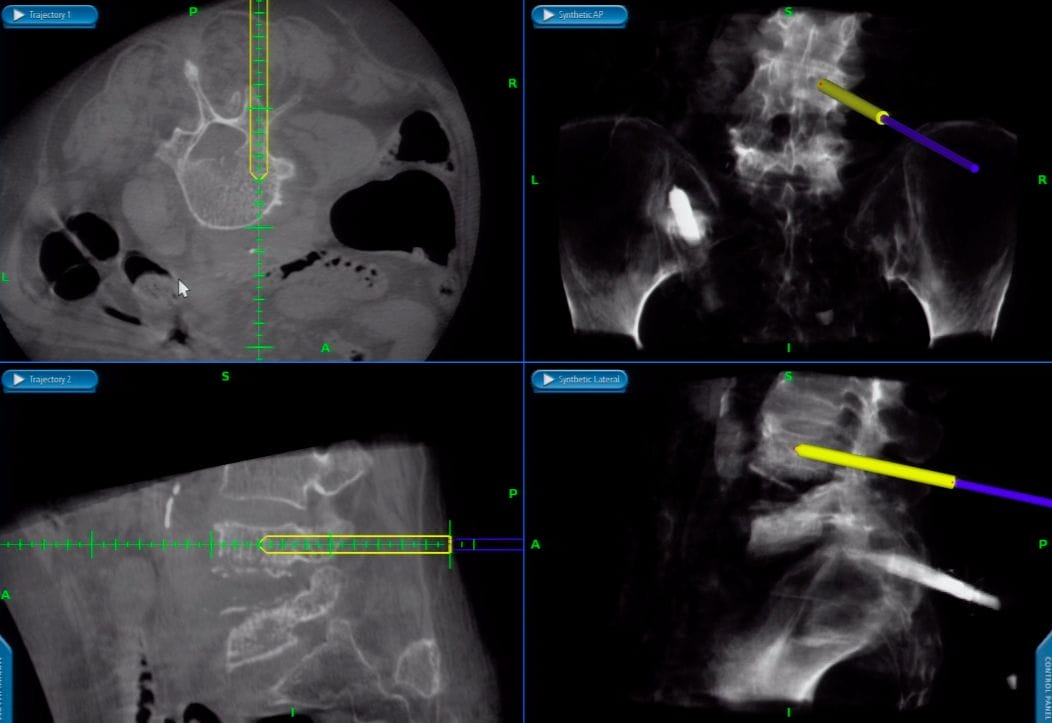

It is not uncommon that implants (screws/ rods/ plates/ cages) may have to be used during spine surgeries. There are several instances when these screws may not be in the correct position, which can result in nerve irritation, compression or damage. Also, an incorrectly placed screw is not as strong a correctly placed one. Though such screw misplacement is uncommon, there is a high risk in complex cases or in presence of deformity. Intra-operative 3d imaging systems (eg. O-arm) coupled with Intra-operative navigation provides the spine surgeon with an accurate 3d reconstructed patient anatomy during the surgery and also guides the surgeon about the accurate placement of screws and implants. It has been proven beyond doubt that presence of Spinal navigation and O-arm significantly improves the accuracy of surgical procedures in general and screw placement, in particular.